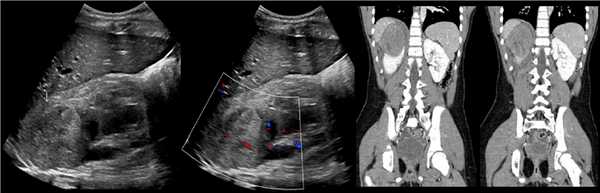

Компьютерная томография (КТ): в проекции устья левого мочеточника и на фоне мочевого пузыря слева определяется дополнительная тень 3,1 x 4,0 x 4,0 см с четкими контурами и плотной стенкой. Мочеточник выше устья расширен до 1 см. Заключение: КТ-картина уретероцеле слева, уретерэктазия слева (рис. 1 б, в).

Рисунок. На УЗИ определяется удвоенная чашечно-лоханочная система, расширена лоханка верхнего сегмента (1) и мочеточник на всем протяжение (2, 3), в мочевом пузыре уретроцеле (4). Полное или неполное удвоение чашечно-лоханочной системы возможно увидеть с помощью КТ-урографии.

Рисунок. КТ-урография (1) показывает неполное удвоение ЧЛС слева: два мочеточника соединяются на входе в таз и единым мочеточником вступают в мочевой пузырь; внутрипузырная часть мочеточника расширена (красная стрелка) — уретероцеле. Уретероцеле хорошо видно на рентгенограммах (2) при экскреторной урографии: правый мочеточник расширен на всем протяжении, дистальный отдел кистозно расширен — «голова кобры».

Рисунок. Уретероцеле (стрелка) на УЗИ и КТ.